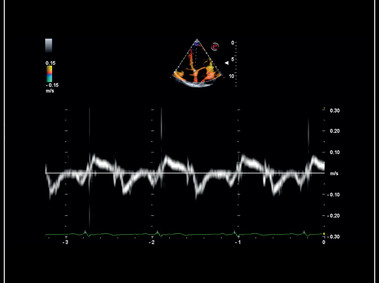

Siêu âm Doppler mô cơ tim với TVM

TVM – Myocardial tissue doppler velocity